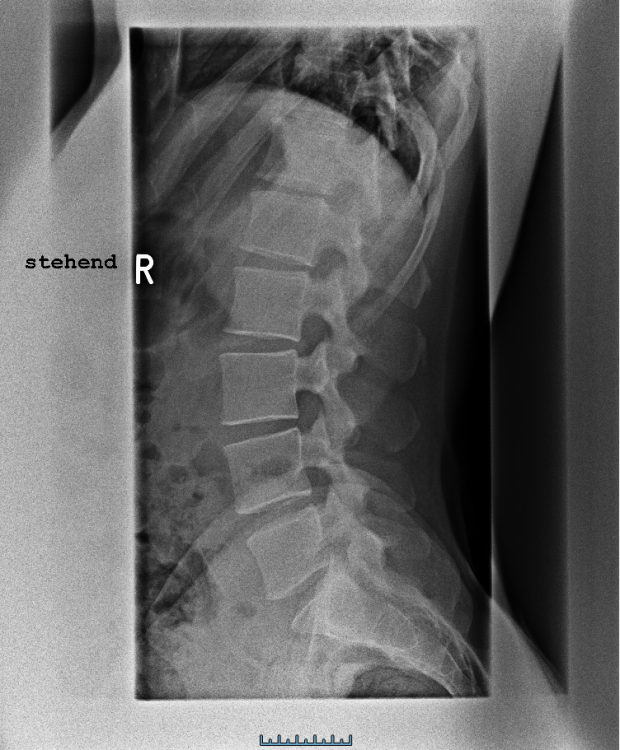

Ich weiß aus der Vergangenheit, dass ich eine fehlende Lordose in der LWS, eine fehlende Kyphose in der BWS und eine fehlende Lordose in der HWS habe. Dies wurde vor 2 Jahren auch durch eine Röntgenaufnahme bestätigt. Seit einigen Monaten arbeite ich zudem an der Verbesserung meiner Haltung. Durch meinen Physiotherapeuten wurde mir damals gesagt, ich solle meine Hamstrings sowie den Hüftbeuger dehnen. Seit ich mich jedoch mit der Materie etwas beschäftige, bin ich etwas verwirrt. Meines jetzigen Wissens nach, kommt eine fehlende Lordose in der HWS vor allem durch eine Verkürzung der Beinrückseite sowie des Bauches und einer Inaktivität der Hüftbeuger sowie des unteren Rückens.

Ich habe mich nun einmal von der Seite fotografieren lassen, um zu schauen, was für eine Haltung ich überhaupt habe. Nun bin ich doppelt verwirrt, weil es aus der seitlichen Ansicht eher so wirkt, als hätte ich eine Hyperlordose in der LWS. Grundsätzlich scheine ich etwas nach vorne zu kippen. Ich habe dann mal geschaut wo sich meine PSIS und ASIS befinden. Mein PSIS ist schon höher als mein ASIS. Aber das müsste doch auf eine Hyperlordose deuten. Wieso wurde auf Röntgenaufnahmen also ein flacher Rücken diagnostiziert? Ich habe mir die Röntgenbilder nochmal angeschaut und die LWS ist tatsächlich eher gerade. Auf der Seitenansicht sieht es jedoch gar nicht so aus. Zudem habe ich einen hervorstehenden Bauch, bin aber überhaupt nicht dick.

Ich habe hier einmal die Röntgenbilder der LWS und BWS sowie den MRT Befund beigefügt. Ich bin mir durchaus bewusst, dass ein fachärztlicher Rat natürlich genau ratsam ist wie eine persönliche Vorstellung bei eben jenem, allerdings war ich wie gesagt, bereits bei etlichen Ärzten und noch möchte ich versuchen, einer künstlichen Bandscheibe aus dem Weg zu gehen.

LWS seitlich.png